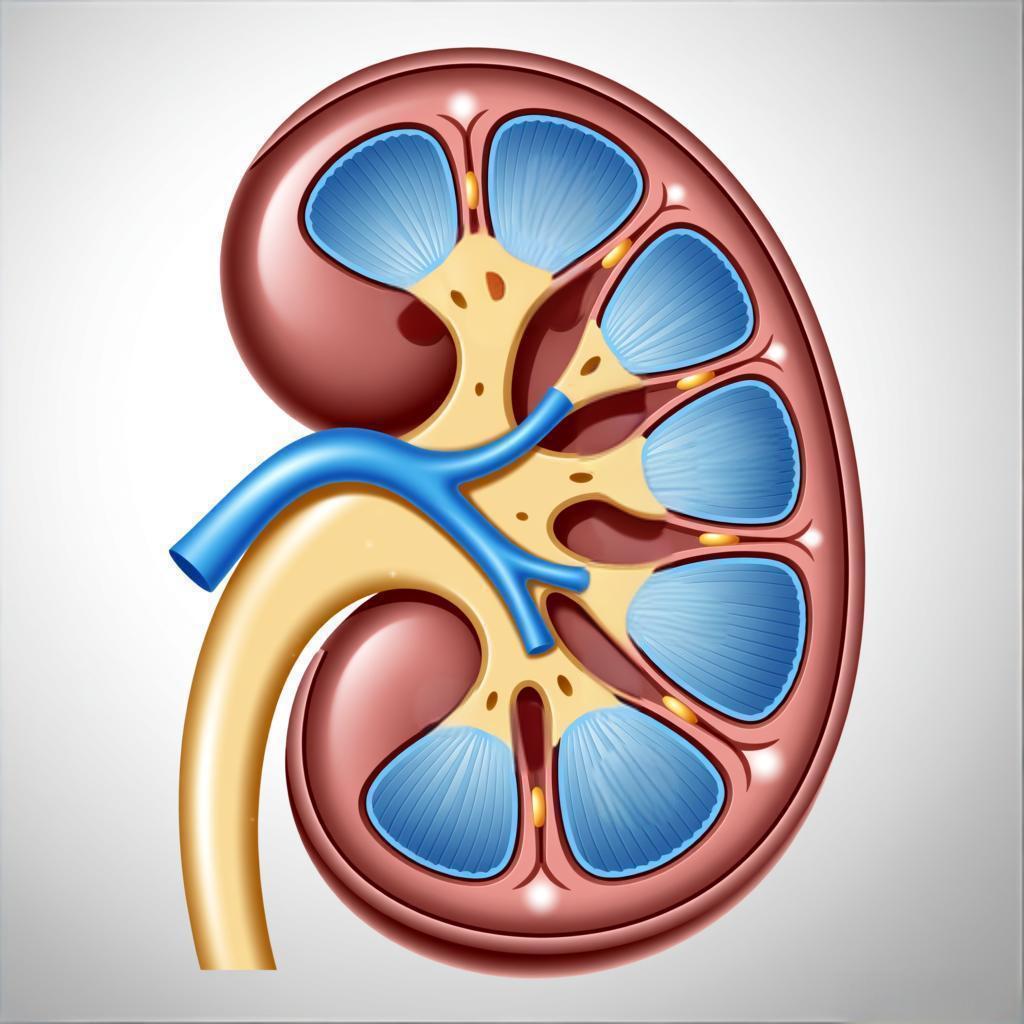

发表于:2025-12-16我们都知道,肾脏每天默默过滤身体血液、排出废物,维持着内环境的稳定。然而,当肾脏上长出囊肿时,其功能...